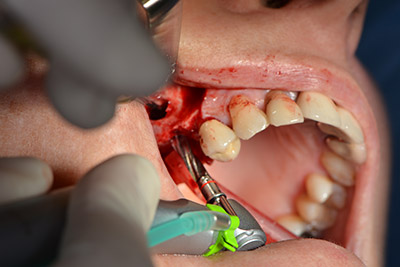

Dunque, l'impianto viene posizionato e l'osso ricostruito. In questo caso, considerate le dimensioni della regione di accrescimento, i microframmenti dell'osso autologo (raccolti con un'apposita cannula di aspirazione in seguito alla perforazione dell'impianto 16 e della fenestrazione 14) vengono combinati con dei materiali di riempimento dell'osso.

Una membrana riassorbibile viene usata come barriera in direzione buccale per contenere l'accrescimento. Infine, vengono applicate suture resistenti alla saliva (da fig. 15 a 19).

Accrescimento con osso autologo

Immagine 15

Immagine 16

Impianto

Immagine 17

Implantologia

Immagine 18

sutura della ferita a prova di saliva

Immagine 19